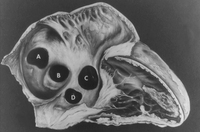

Subtipos de defeitos do septo atrial. (A) seio venoso; (B) ostium secundum; (C) ostium primum; (D) seio coronário sem teto

Mayo Clinic Foundation